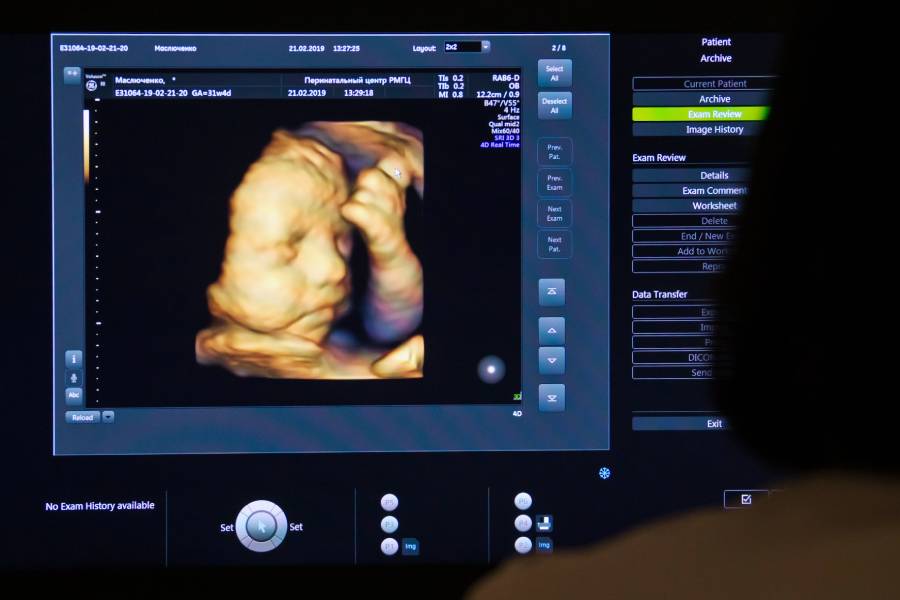

Монитор во время УЗИ беременной женщины в перинатальном центреФото: Сергей Мальгавко / ТАСС